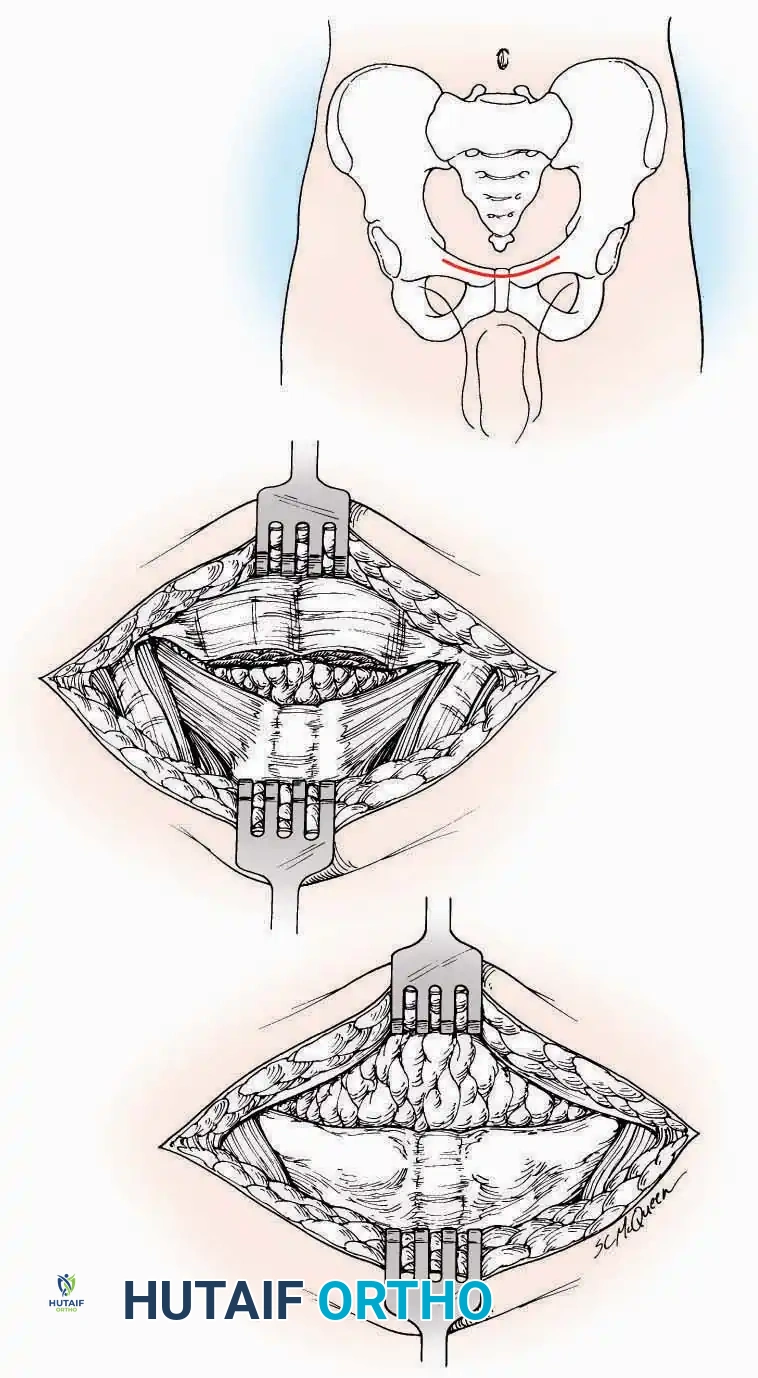

SURGICAL APPROACHES TO THE TARSUS AND ANKLE

Anterolateral Approach

The anterolateral approach is widely considered the "universal incision" for the foot and ankle. It provides unparalleled access to the ankle joint, the talus, and the majority of the tarsal articulations, while safely avoiding the major anterior neurovascular bundle. The only tarsal joints inaccessible via this route are the naviculocuneiform joints (specifically the medial and intermediate).

Indications: Total talectomy, triple arthrodesis, ankle arthrodesis, and open reduction of complex talar neck fractures.

Surgical Technique:

* Incision: Begin over the anterolateral aspect of the leg, medial to the fibula and 5 cm proximal to the ankle joint line. Carry it distally over the joint, crossing the anterolateral aspect of the talar body and the calcaneocuboid joint, terminating at the base of the fourth metatarsal.

* Superficial Dissection: Incise the superficial fascia and the superior and inferior extensor retinacula down to the periosteum of the tibia and the ankle joint capsule.

* Vascular Ligation: This trajectory usually requires the identification and ligation of the anterolateral malleolar and lateral tarsal arteries.

* Nerve Protection: Retract the skin edges carefully. Identify and protect the intermediate dorsal cutaneous branches of the superficial peroneal nerve (SPN), which frequently cross the distal aspect of this incision.

* Muscle Management: Identify the origin of the extensor digitorum brevis (EDB) muscle on the lateral calcaneus. Divide it in the direction of its fibers, or detach its origin entirely and reflect it distally to expose the subtalar and calcaneocuboid joints.

* Deep Exposure: Retract the extensor digitorum longus (EDL) tendons, the dorsalis pedis artery, and the deep peroneal nerve (DPN) medially. Incise the anterior ankle capsule to expose the tibiotalar joint.

* Tarsal Exposure: Expose the talonavicular joint by dissecting deep to the extensor tendons and incising its capsule transversely. Continue laterally through the capsule of the calcaneocuboid joint. By excising the fat pad within the sinus tarsi (lateral and inferior to the talar neck), the posterior facet of the subtalar joint is brought into direct view.